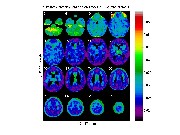

Or we might want to compare the t statistics on all tasks at a range of slices (64 65,66) that cover the region of greatest activation (rows are tasks, columns are slices):

m=['c:/keith/fMRI/manou/cbf_non_kin_smoother_1_t.mnc';

'c:/keith/fMRI/manou/cbf_non_kin_smoother_2_t.mnc';

'c:/keith/fMRI/manou/cbf_non_kin_smoother_3_t.mnc';

'c:/keith/fMRI/manou/cbf_non_kin_smoother_4_t.mnc']

clf;

view_slices(m,mask,0.65,64:66,1:4)

![[Click to enlarge image]](figs_pet_tn/fignormt1234.jpg)